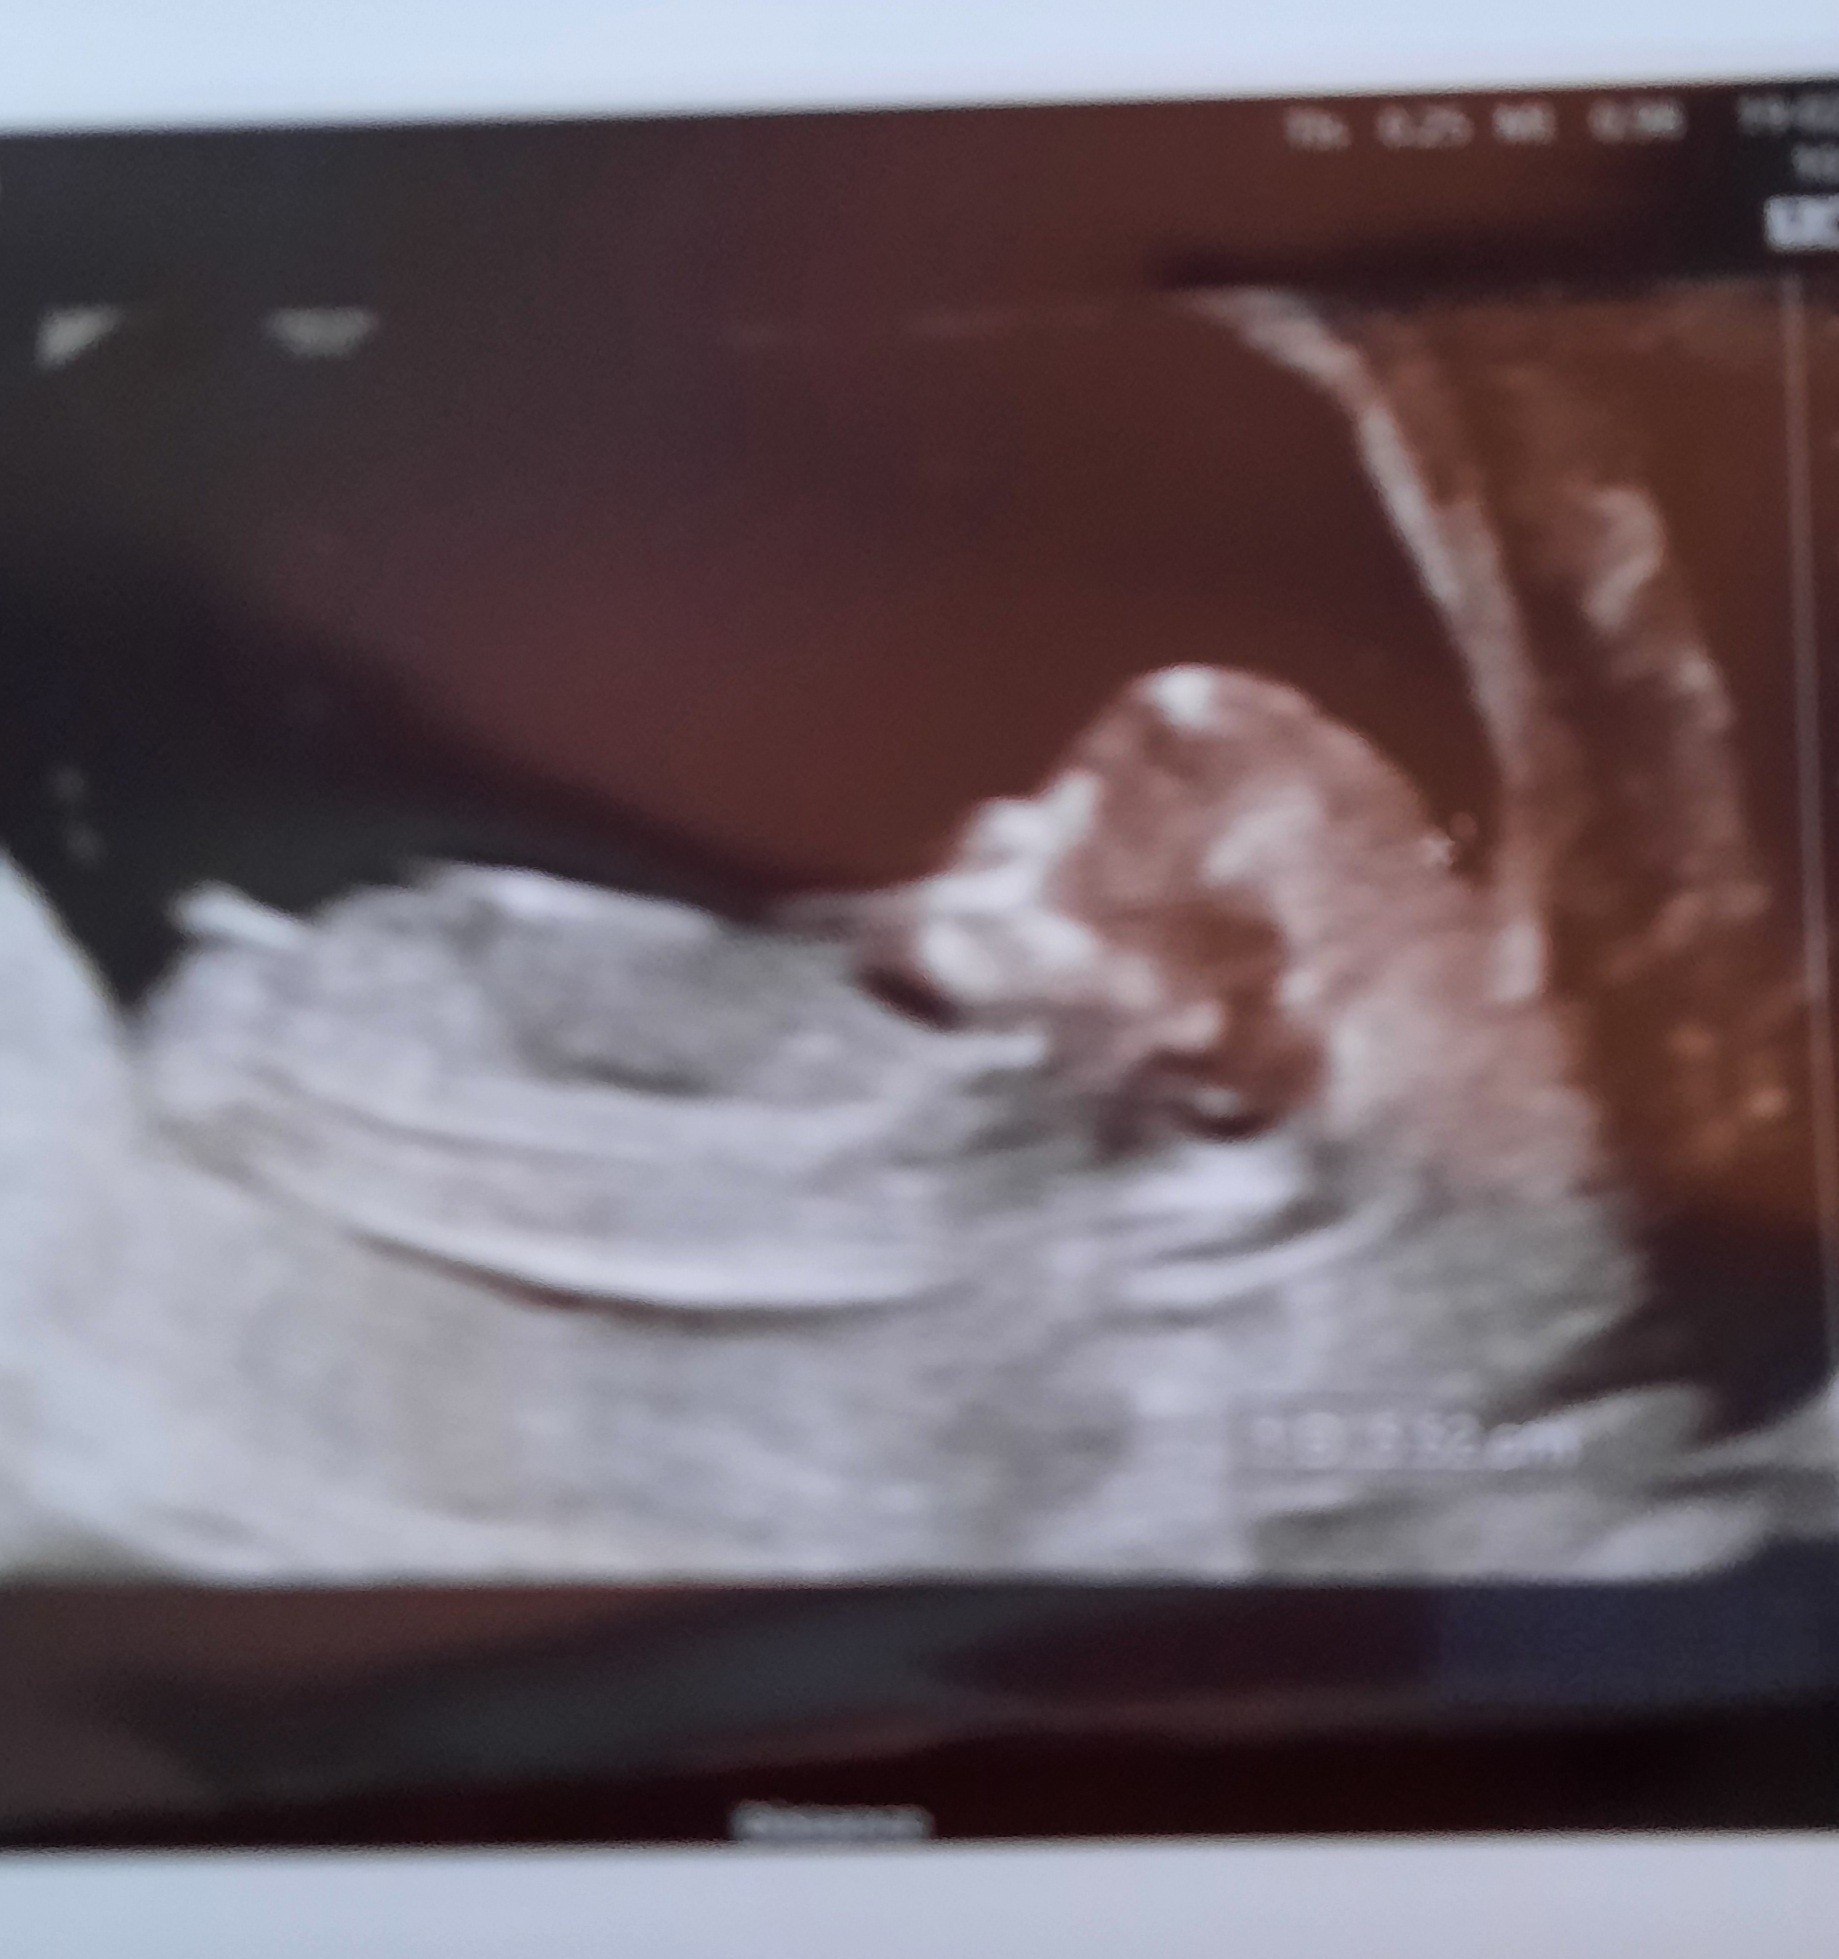

• 20210219_183639.jpg

20210219_183639.jpg

1,5 MB · Wyświetleń: 80